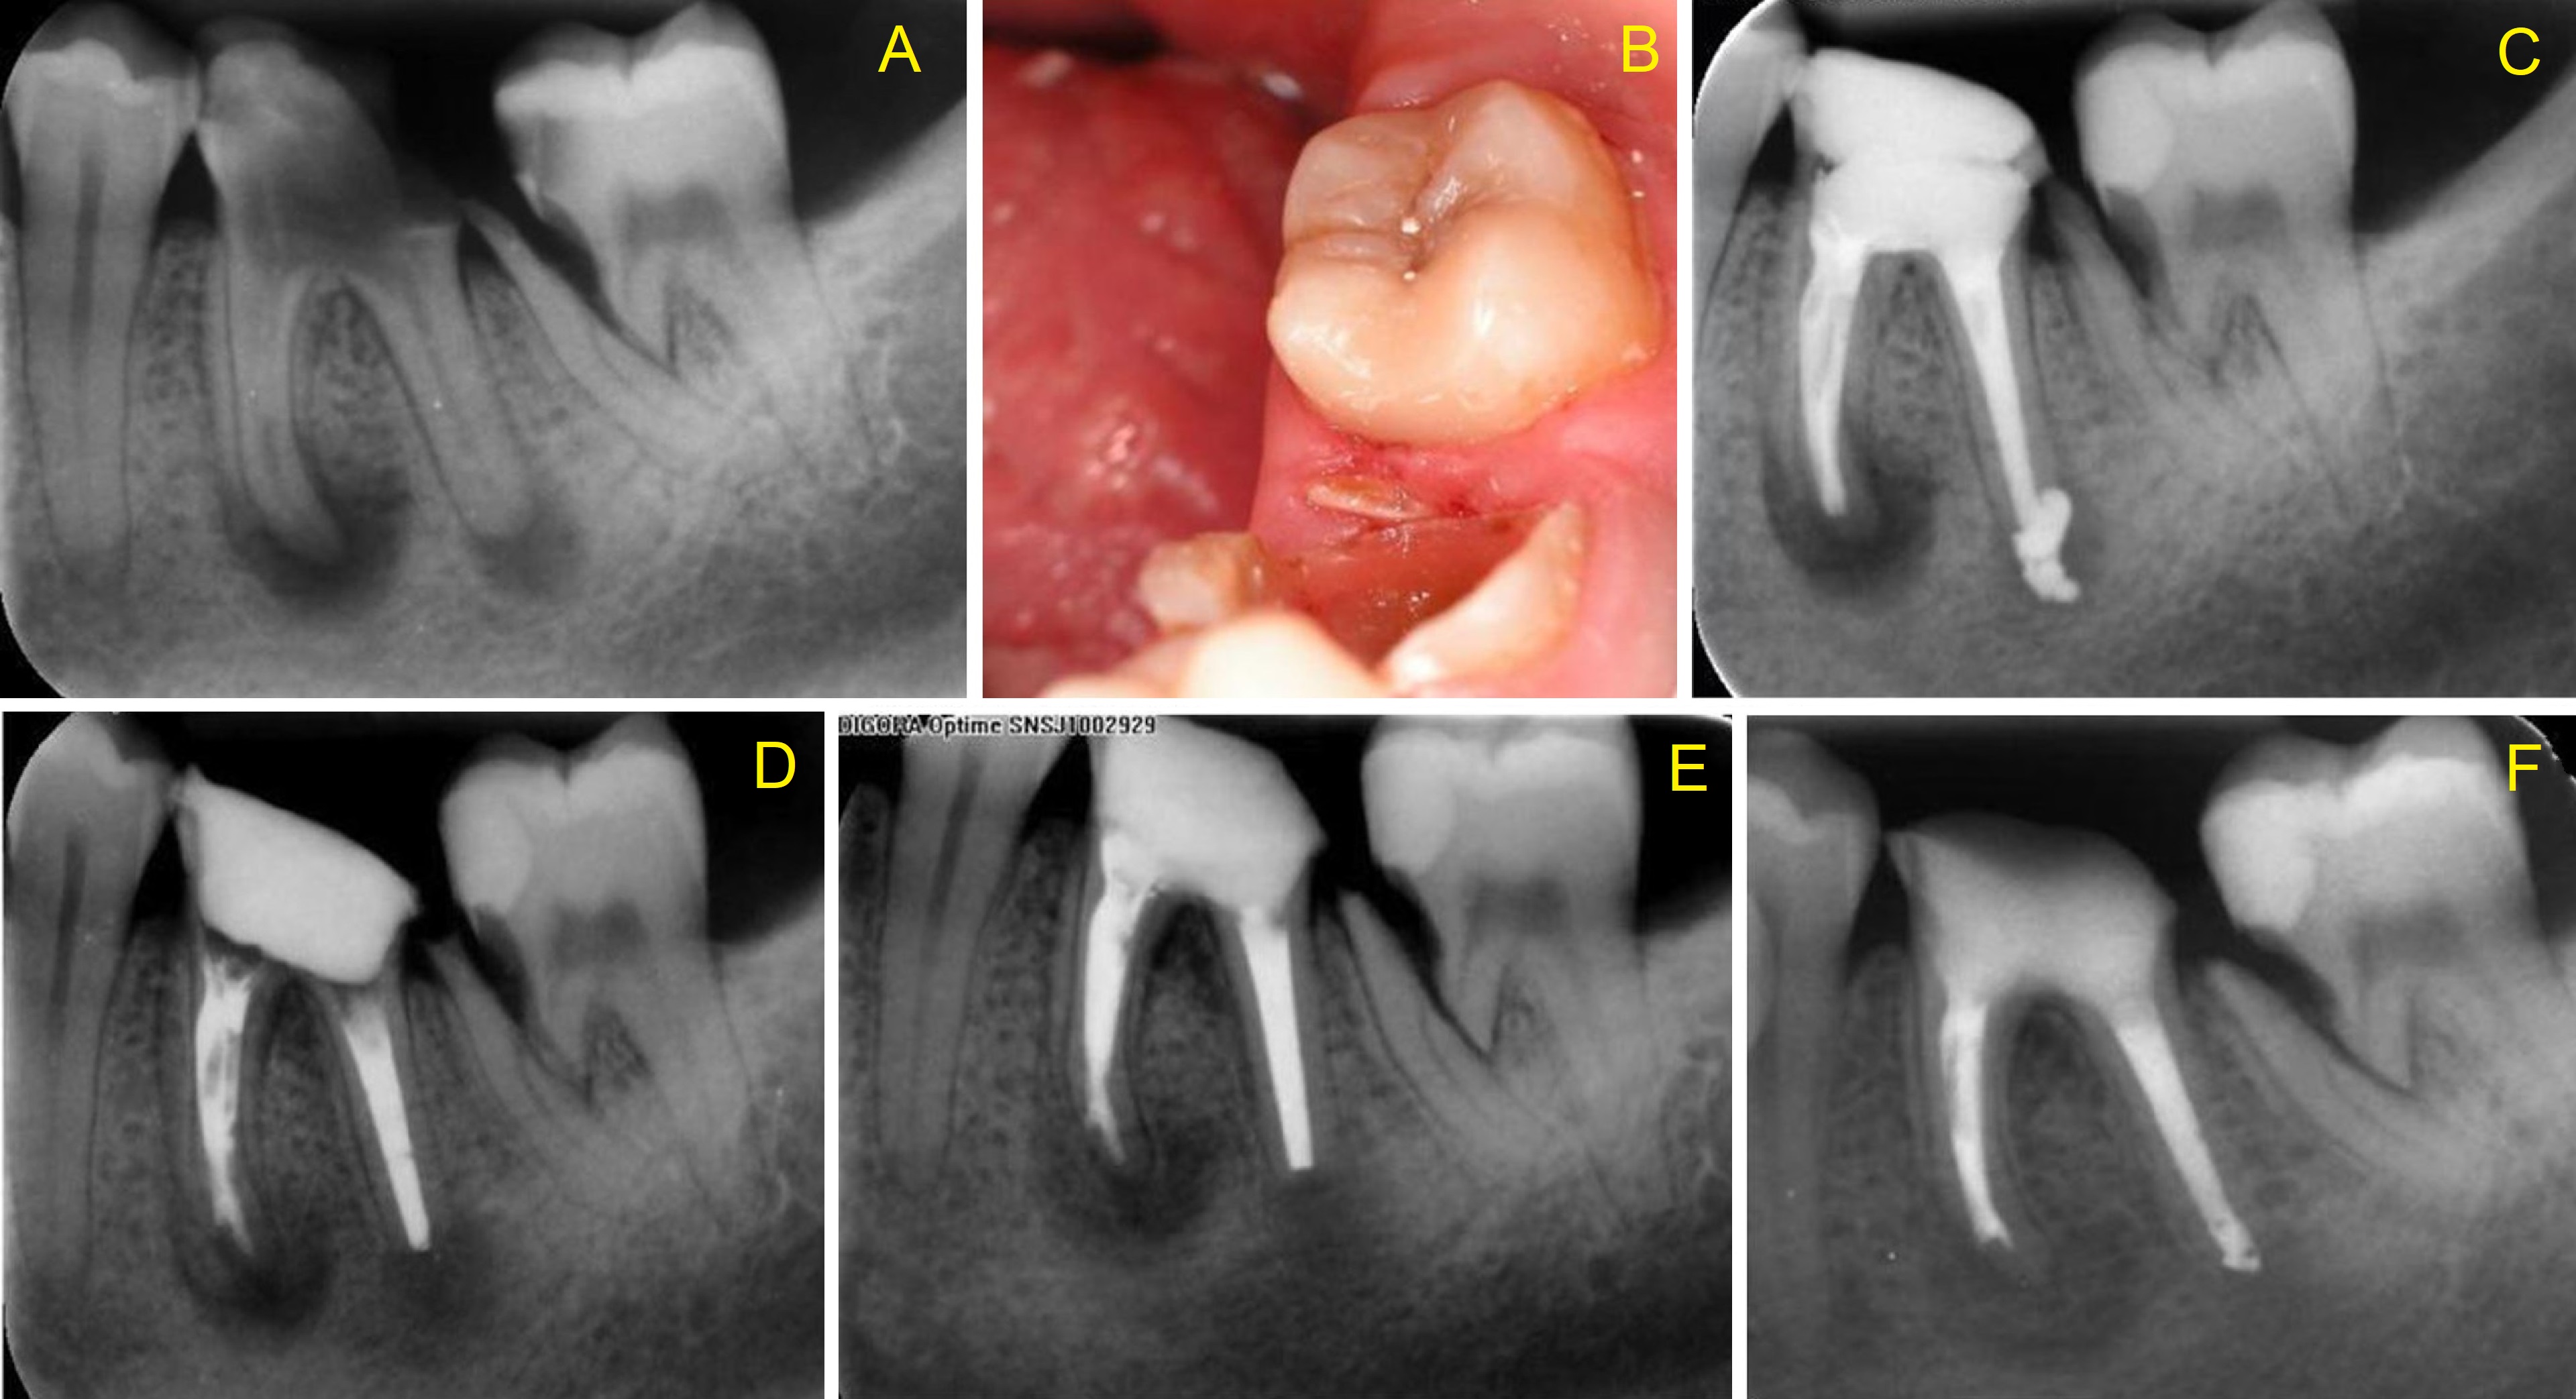

An oblique crown-root fracture of the mesial root of molar with vital pulp – a case study

An oblique crown-root fracture was detected incidentally in the cervical middle third of the mesial root of a non-endodontically treated second lower right molar. Because the tooth was asymptomatic, the pulp responded positively to testing and no periapical pathosis was detected, an endodontic treatment was not indicated. Considering the unusual condition of tooth 47, substantial efforts were made to save tooth 46, which had been extensively destroyed by caries. A control cone beam computed tomography (CBCT) acquired 12 months after completion of the endodontic treatment of tooth 46 revealed almost complete resolution of the periapical pathosis in the first right molar, no changes in the fracture line and no periradicular radiolucency in the second right molar. The loss of this tooth could have resulted in postextraction atrophy of the alveolar bone and loss of support for the fractured root of the adjacent tooth.